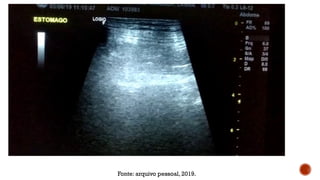

Fonte: arquivo pessoal, 2019.